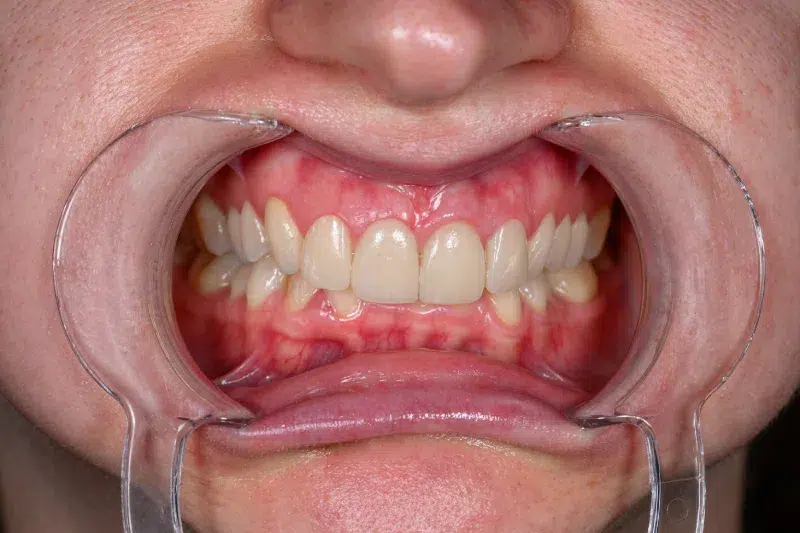

Înainte

Caz de estetică dentară – Fațete ceramică presată E-Max

Provocarea acestui caz a fost în prepararea minim invazivă a dinților centrali rotați și a obține o formă și o culoare cât mai naturală, pacienta dorind un caz de estetică dentară ce să nu fie observabil.

Pacienta a beneficiat de corecție gingivala cu laser pentru uniformizarea asimetriilor gingivale, tratamente endodontice de canal sub microscop, obturațiile vechi (plombe) schimbate cu materiale de compozit cu particule nanoceramice, și fațete dentare din ceramică presată E-Max.

Termen de finalizare 2 săptămâni de la amprentarea finală.